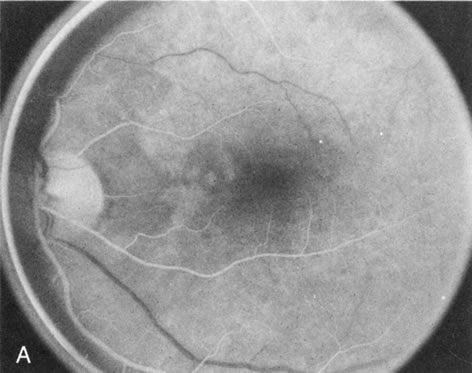

In the early stages of choroideremia, before choroidal atrophy is funduscopically obvious and when the picture resembles RP, FA indicates diffuse choroidal atrophy throughout the entire retina. Only the macular area remains preserved (Fig. 4A and B).

Fig. 4. Choroideremia and choroideremia carrier. A. The choroidal atrophy in this affected male is not apparent in the fundus. B. However, the angiogram shows diffuse atrophy of the choriocapillaris with persistent visualization of the larger choroidal vessels. C. This carrier female has peripapillary choroidal atrophy and diffuse pigment mottling. D. The patchy areas of focal choroidal atrophy that occasionally occurs in carriers is evident on angiography.

The typical carrier female, with focal or diffuse pigment mottling, does not show choroidal atrophy. However, a few carrier females have a more severe form with focal areas of choroidal atrophy. The presence of these areas, and possible progression, can be documented by FA (Fig. 4C and D). These carriers exhibit a mosaicism, which is explained by the Lyon hypothesis of random X-chromosome inactivation.